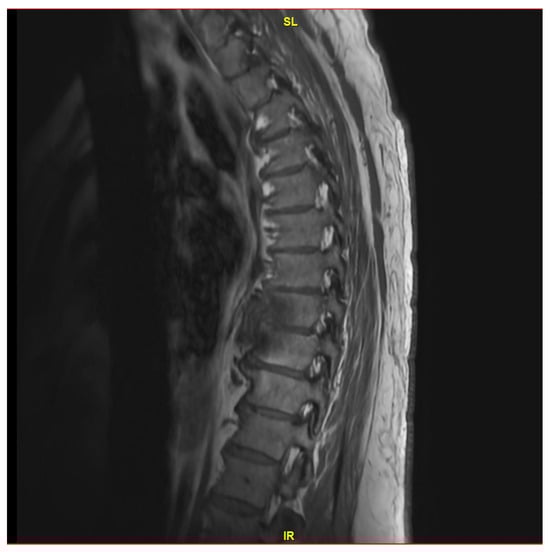

He demonstrated progressive improvement in his pain on ceftriaxone without the need for narcotic analgesics. He underwent a third MRI after 6 weeks of treatment (on 29 August 2023), which showed the known changes at T8 and T9, with near resolution of the fluid within the T8-T9 disc (Figure 2). Due to improvement but continued destructive changes and edema, the decision was made to pursue oral therapy after completion of IV ceftriaxone with oral cefuroxime 500 mg q.12 h, which was initiated on 14 September 2023.

Figure 2. MRI thoracic spine with and without IV contrast revealing redemonstration of T8-T9 diskitis with mild improvement of paraspinal/epidural phlegmon.